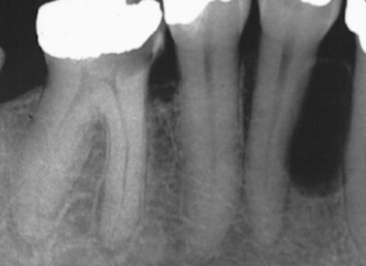

What is the Green Dot?

Submandibular Fossa

What is the Purple Dot?

Radicular Cyst

What is the dental anomaly?

Healing Cyst

What are the Radiographic Characteristics of this Healing Cyst?

New bone forms at the original cortex and grows toward the center